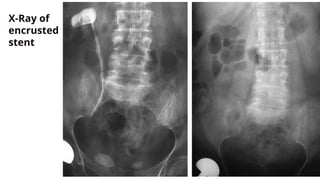

X-Ray of

encrusted

stent

encrusted stent

Aravantinos E, Gravas S, Karatzas AD, Tzortzis V, Melekos M. Forgotten, encrusted ureteral stents:

a challenging problem with an endourologic solution. J Endourol. 2006 Dec;20(12):1045-9.